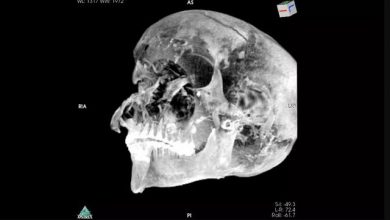

راز مرگ فرعون مصری مشخص شد

محققان میگویند شواهد جدید نشان میدهد فرعون مصری که با نام تائو دوم شناخته میشود در میدان نبرد کشته شده…